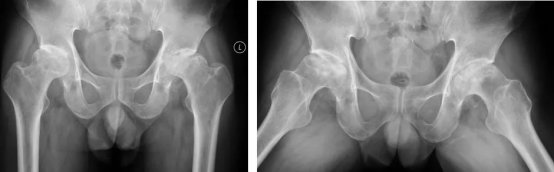

X线检查

X线检查是首选的检查方法,可以诊断ARCO II期以上的股骨头坏死,但是对于超早期(ARCO I期)的患者不能发现。

股骨头缺血性坏死X线表现